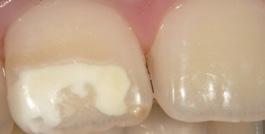

CBCT imaging is the most comprehensive tool for adding procedures and efficiencies by providing predictable diagnostics. For example, with the advancement of low-dose 3D imaging, the concept of a 3D PA (replacing a PA for diagnosis) is often a better clinical choice.

According to a study from Clinical Research 2017, 50% of small volume scans found asymptomatic abnormalities. Studies of large FOV CBCT scans show the prevalence of incidental finding to be greater than 90%. During 3D training, we often find these infections and other asymptomatic issues on the scans. The direct connection between oral health and overall systemic health emphasizes the importance of early diagnosis.

Surgical guides are amazing tools to overlay your cone beam (hard tissue) with your IO scan (soft tissue) for restorative and implant-driven surgical planning. With this technology, you can digitally plan your case and have a surgical guide giving you the confidence to add these procedures to your own practice.

JMartin@BurkhartDental.com 253.273.5890 Joe Erbaugh Eastern Washington Clinical Digital Specialist JErbaugh@BurkhartDental.com 503.341.8730 STL integrated with DICOM for surgical guide design BurkhartDental.com